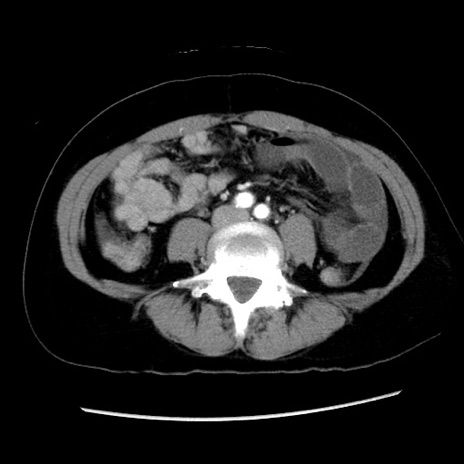

症例10(横断像)

【症例】 50歳代女性

【主訴】 腹痛

【現病歴】前日生レバーを食べた。今朝に排便あり。 昼前に突然発症の腹痛を生じ、当院救急外来を受診した。

【既往歴】 子宮筋腫にてで子宮全摘後

【身体所見】 意識清明、腹部:平坦、軟、下腹部やや左を中心に圧痛・反跳痛あり、筋性防御あり

【データ】WBC 7800、CRP 0.07